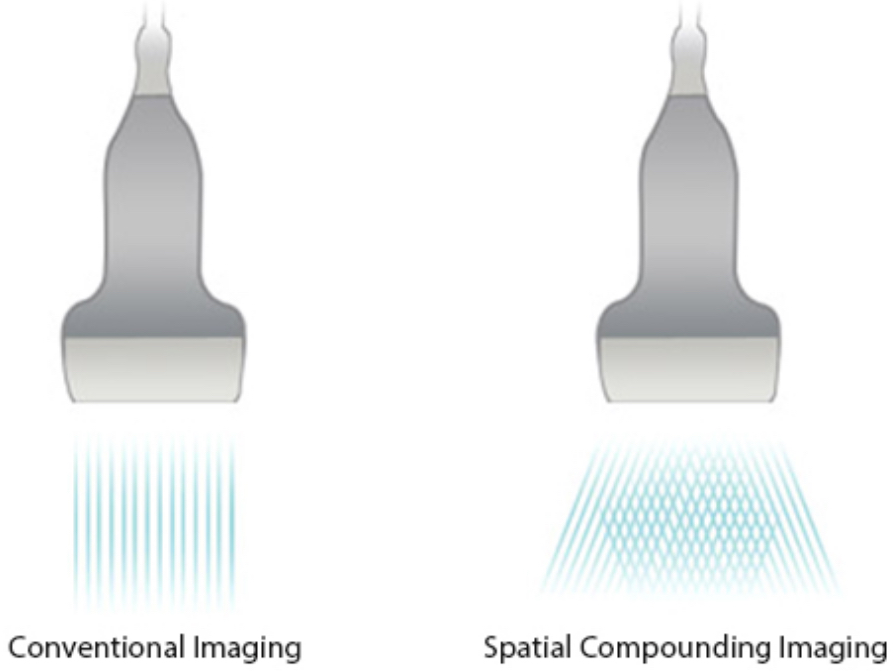

iBeam?

Permite el uso de varios ĂĄngulos de exploraciĂłn para formar una sola imagen, lo que ofrece una mayor resoluciĂłn de contrastes y una mejor visualizaciĂłn.